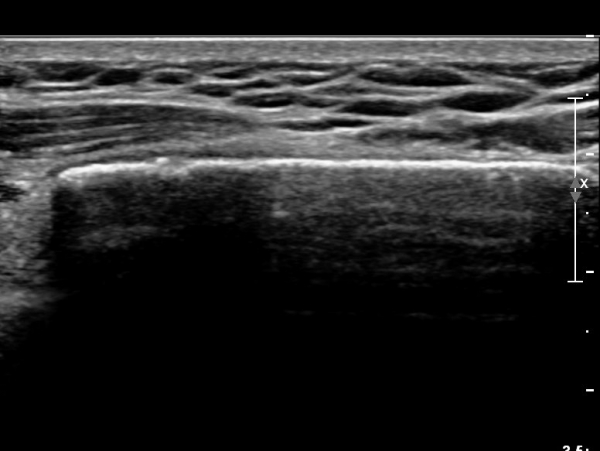

ÃÊÀ½ÆÄ °Ë»ç : ¼Õ¸ñ ¼ö±Ù°ü ±ÙÀ§ºÎ Ⱦ´Ü¸é°Ë»ç¿¡¼­ Äá¾Ë»À Ç¥ÃþÀ¸·Î ¾à°£ÀÇ ¿¬ºÎÁ¶Á÷ ºÎÁ¾ÀÌ °üÂûµÊ(»çÁø 1).